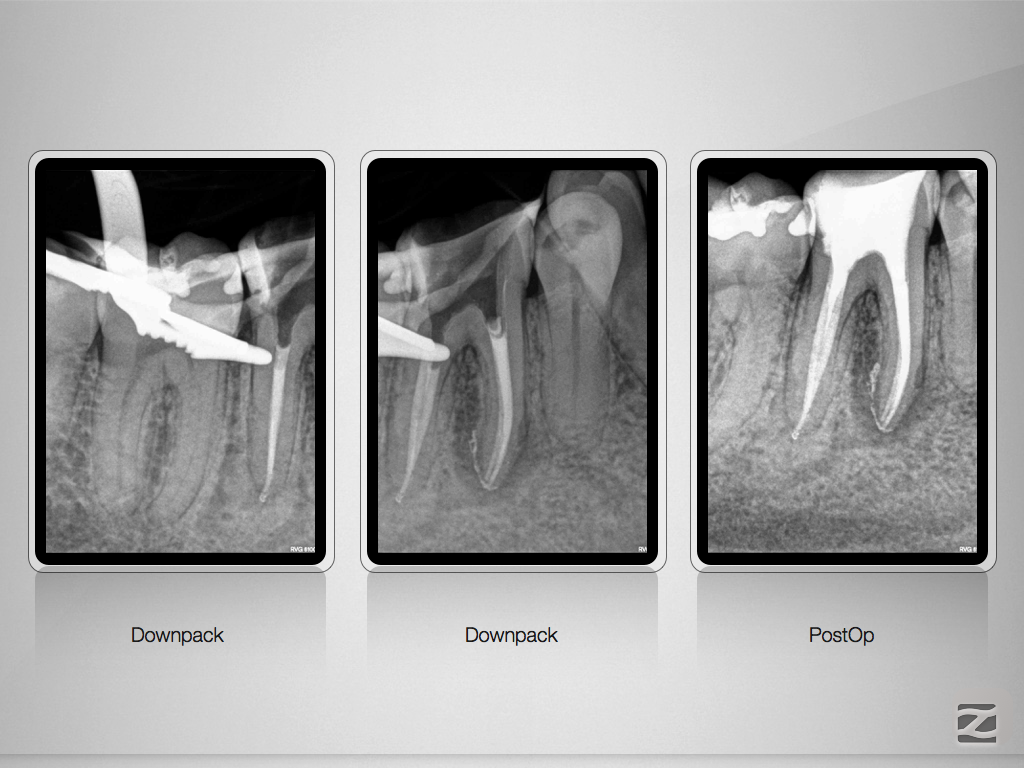

46D.006

Partielle Pulpanekrose